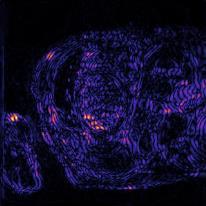

Recently, deep neural networks have greatly advanced undersampled Magnetic Resonance Image (MRI) reconstruction, wherein most studies follow the one-anatomy-one-network fashion, i.e., each expert network is trained and evaluated for a specific anatomy. Apart from inefficiency in training multiple independent models, such convention ignores the shared de-aliasing knowledge across various anatomies which can benefit each other. To explore the shared knowledge, one naive way is to combine all the data from various anatomies to train an all-round network. Unfortunately, despite the existence of the shared de-aliasing knowledge, we reveal that the exclusive knowledge across different anatomies can deteriorate specific reconstruction targets, yielding overall performance degradation. Observing this, in this study, we present a novel deep MRI reconstruction framework with both anatomy-shared and anatomy-specific parameterized learners, aiming to "seek common ground while reserving differences" across different anatomies.Particularly, the primary anatomy-shared learners are exposed to different anatomies to model flourishing shared knowledge, while the efficient anatomy-specific learners are trained with their target anatomy for exclusive knowledge. Four different implementations of anatomy-specific learners are presented and explored on the top of our framework in two MRI reconstruction networks. Comprehensive experiments on brain, knee and cardiac MRI datasets demonstrate that three of these learners are able to enhance reconstruction performance via multiple anatomy collaborative learning.

翻译:最近,深心神经网络大大推进了未经充分取样的磁共振成像(MRI)重建,其中大多数研究都遵循单一解剖一个网络的方式,即每个专家网络都经过特定解剖学的培训和评价。除了在培训多种独立模型方面效率低下之外,这种公约忽视了不同解剖学中共享的、可相互受益的解析知识。为了探索共享知识,一种天真的方法是将各解剖学家的所有数据结合起来,以训练一个全方位网络。不幸的是,尽管存在共享的解析知识,但我们发现,不同解剖学的独家知识可以恶化具体的重建目标,导致总体性能退化。在这项研究中,我们提出了一个新型的深度解剖重建框架,既有解剖学共享知识,又具有具体的解剖学参数,目的是“寻找共同的土壤,同时保留不同解剖学家之间的差异。此外,主要的解剖学学习者将接触不同的解剖学数据,通过多种解剖学重建的模型,并用不同的解剖学研究者将数据展示出一个全方位基础。